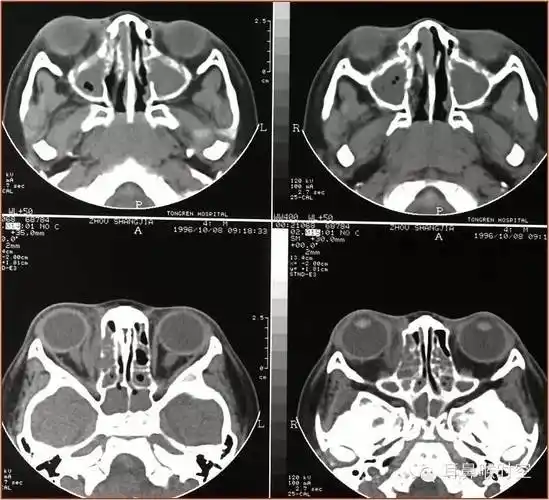

急性鼻窦炎并发症脓肿骨壁破坏ct:鼻窦密度增高water氏位:窦腔混浊,液